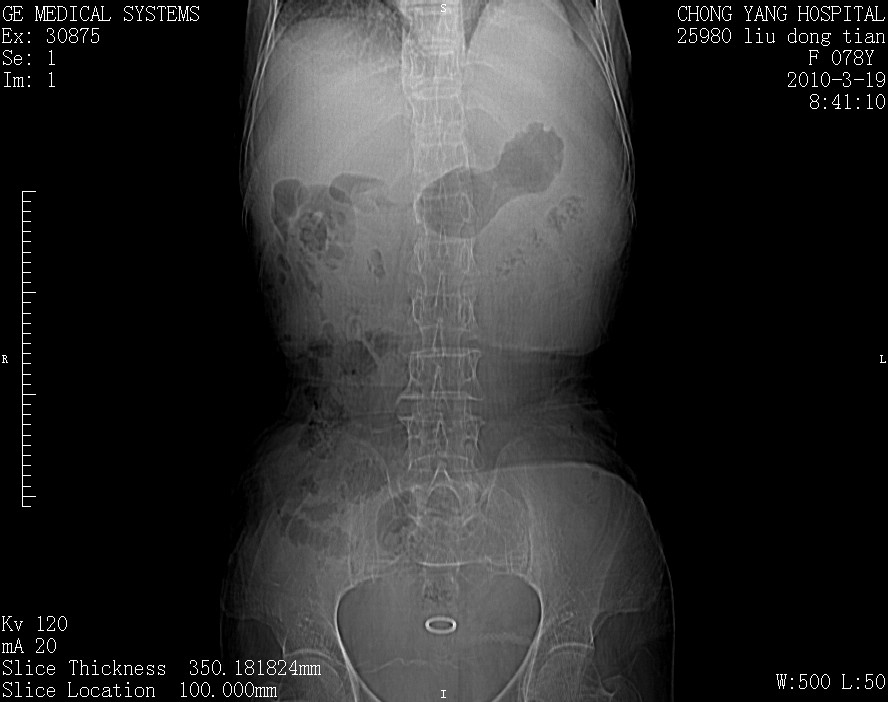

标题: CT25199:F 78Y 腹胀半年 消瘦乏力 [打印本页]

标题: CT25199:F 78Y 腹胀半年 消瘦乏力

胆囊壁增厚并明显强化,胆囊癌伴多发转移瘤可能性大,淋巴瘤不除外,右肾囊肿,胸腹水.

考虑nhl,肝、脾、腹膜腔及腹膜后多发淋巴结受侵,腹水,右肾囊肿,慢性胆囊炎,右侧少量胸腔积液。

胰头有肿块形成,胰头ca伴肝脾、腹膜腹膜后转移

胆囊有软组织影有强化,支持胆囊癌,肝脾、腹膜后淋巴结转移。

nhl的淋巴结多围绕主动脉,而且主动脉会移位,所以不考虑nhl。

分开来讲:肝左叶、尾叶病灶有不均强化像肝癌;

脾脏病灶无强化,像多发囊肿或淋巴管瘤,不除外淋巴瘤(低强化);

胆囊增生性病变:胆囊癌,腺肌增生症,慢性胆囊炎;

肝门、胰腺头、腹膜后多个团块: 淋巴瘤,转移;

腔静脉肝内段细小有无布加可能?

一元论最好了 淋巴瘤所致改变; 胆囊癌转移不像,胆囊周围肝组织清晰,肝癌淋巴结转移?三元论都不止。

胰头ca伴肝脾、腹膜腹膜后转移!

最后报的胰头癌多发转移,脾脏单独考虑囊肿或淋巴管瘤。